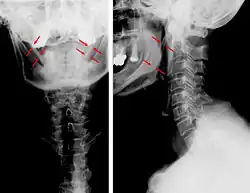

| Anteroposterior and lateral radiographs of cervical spine showing ossification of the stylohyoid ligament on both sides | |

-

Radiograph, lateral view showing elongated stylohyoid process and stylohyoid ligament ossification -

Radiograph, lateral view showing joint-like formation in ossified stylohyoid ligament -

CT scan, coronal section showing bilateral extended styloid process and stylohyoid ligament ossification (incidental finding) -

3D-reconstructed CT scan showing bilateral stylohyoid ligament ossification -

3D reconstructed CT scan showing elongated styloid process (right side)

Diagnosis is suspected when a patient presents with the symptoms of the classic form of "Eagle syndrome" e.g. unilateral neck pain, sore throat or tinnitus. Sometimes the tip of the styloid process is palpable in the back of the throat. The diagnosis of the vascular type is more difficult and requires an expert opinion. One should have a high level of suspicion when neurological symptoms occur upon head rotation. Symptoms tend to be worsened on bimanual palpation of the styloid through the tonsillar bed. They may be relieved by infiltration of lidocaine into the tonsillar bed. Because of the proximity of several large vascular structures in this area this procedure should not be considered to be risk free.

Imaging is important and is diagnostic. Visualizing the styloid process on a CT scan with 3D reconstruction is the suggested imaging technique.[13] The enlarged styloid may be visible on an orthopantogram or a lateral soft tissue X ray of the neck.